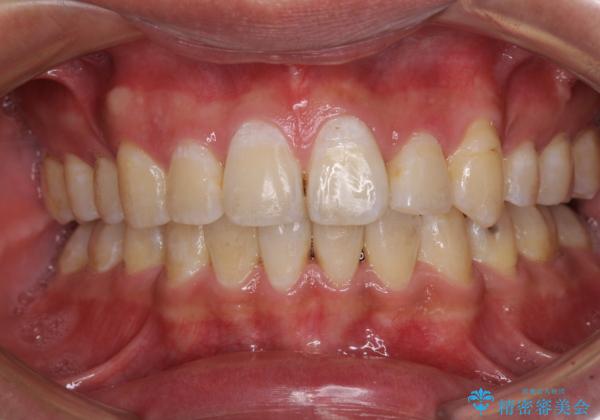

- 前歯の叢生と八重歯を気にして来院された患者様です。

叢生が強く、奥歯の咬合も左右差が大きかったため、上下左右4本を抜歯して、ワイヤー矯正を行うこととしました。